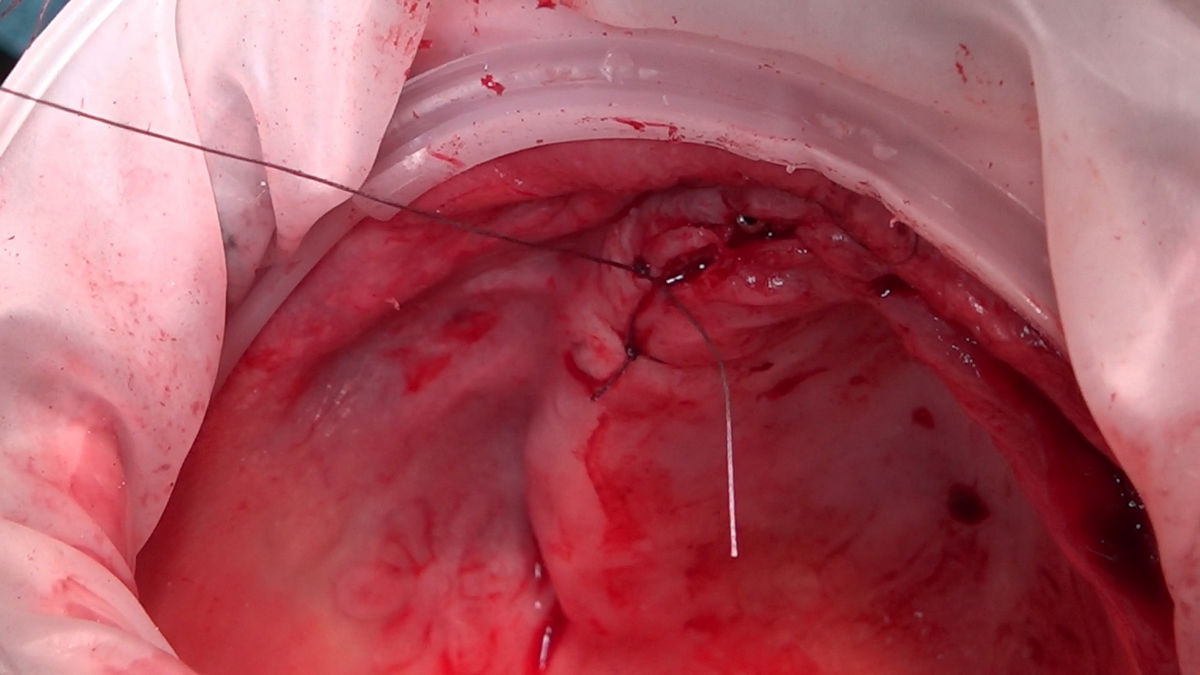

Chirurgia implantologiczna to temat wiodący 5 Sesji X Sezonu Practiculum Implantologii, która się odbyła 23-24 października 2020 roku. Bierze w nim udział 16 adeptów implantologii stomatologicznej. Zabiegi z udziałem Pacjentów jak zwykle poprzedziło omówienie i planowanie, tym bardziej, że zgodnie z planem wykonana została implantacja z wykorzystaniem szablonu chirurgicznego, który przygotowało laboratorium dentystyczne Wiligała Lab. Kursanci wykonywali szereg zabiegów implantologicznych i chirurgicznych oraz regeneracyjnych z zastosowaniem PRF, w tym sinus lift. Przeprowadzali je pod kierunkiem Lidera Umiejętności Implantologicznych dr n.med. Violetty Szycik, która wysoko oceniła wykonanie zabiegów.